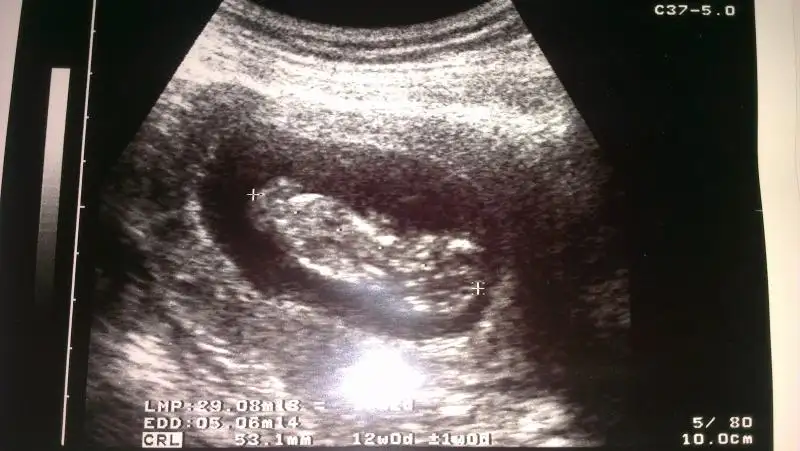

Eki Görüntüle 861358 10 hafta 3 günlük

bebeklerin cinsiyeti nedir acaba? biri yengemin biri benim

Bacagi nubunu saklamis canm ya in haftalikta sanki kiz gibi ama kucuk oluyo ozamnda ins baska fotolariyla goruruz